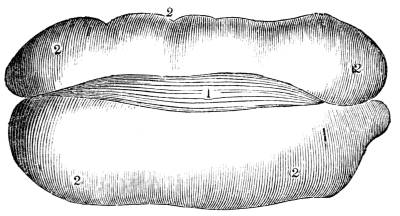

Fig. CXXXVIII.—

View of the Bronchial Tubes terminating

in Air vesicles.

Fig. 138.Fig. 139.

External view.—1. Bronchial tube. 2. Air vesicles. Fig.

139. The same laid open.